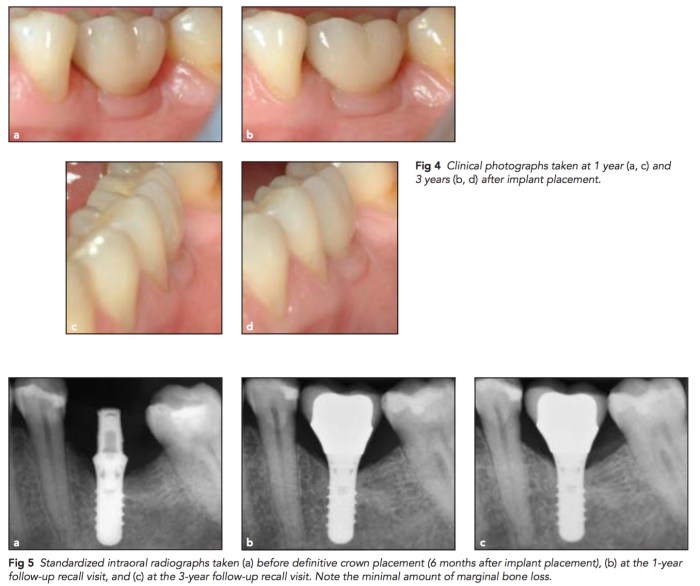

在20個有shallow buccal bone dehiscence(小於3mm),利用Straumann Standard Plus,將implant abutment connection放在bone之上2mm, 加上buccal side flap之內縫上一塊CT graft。在追蹤三年後仍然保持良好。

那為什麼不可以用bone level加上長的healing abutment?因為這個團隊認為這樣bone 會繼續向下掉,連帶拖累soft tissue。我的專長畢竟是在硬組織的方面,軟組織的部分真的要再多進修。